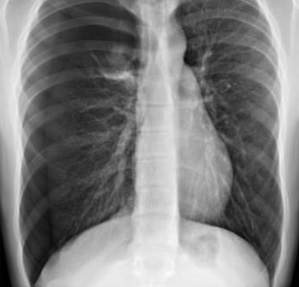

Q

¿Cuál es el dx?

A

Neumotórax